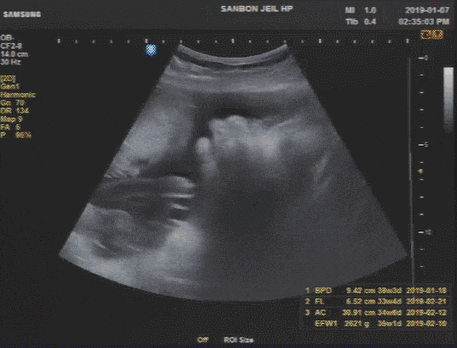

2019.01.28 [39w5d] 목욕재계/김밥식사 후 9;30 병원 진료를 왔다 아마도 마지막 진료가 되겠지만? 입원은 ...